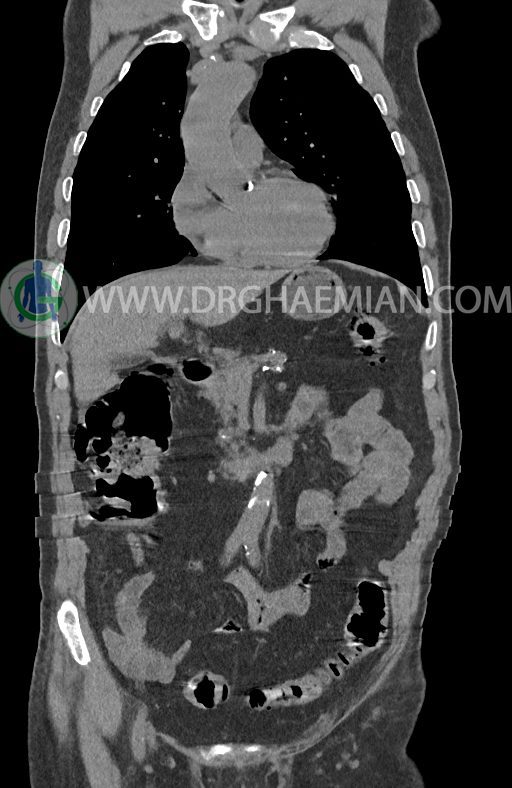

در سی تی اسکن اسپیرال ریه ها و مدیاستن، شکم و لگن با و بدون کنتراست وریدی (مولتی دیدکتور 16 با مقاطع ظریف و بازسازی کرونال) :

–افزایش ضخامت تومورال دیستال مری و GEJ در سگمانی به طول 4cm-5cm (T2 or T3)

–آتروفی نسبی پانکراس همراه با فوکوس های کلسیفیه ی منتشر پارانشیم مطرح کننده ی پانکراتیت مزمن

-CBD بسیار دیلاته (16mm) همراه با دیلاتاسیون مجاری داخل کبدی سنترال بدون شواهد سنگ یا توده در مسیر

–کیست های کورتیکال متعدد هر دو کلیه به بزرگترین قطر 56mm

–پروستات به دیامتر عرضی بزرگ حاوی فوکوس کلسیفیه

نتیجه : T(2or3)/N2/M0